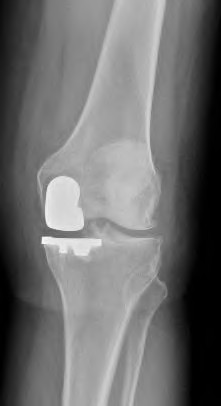

A 72-year-old female presents with progressive left thigh and knee pain for the last year. 5 years ago she sustained a femoral neck fracture treated with the implant seen in Figures A-C (current radiographs). The thigh pain is worse with weight-bearing. C-reactive

protein and erythrocyte sedimentation levels are within defined limits. Which of the following is the most likely cause of her pain?